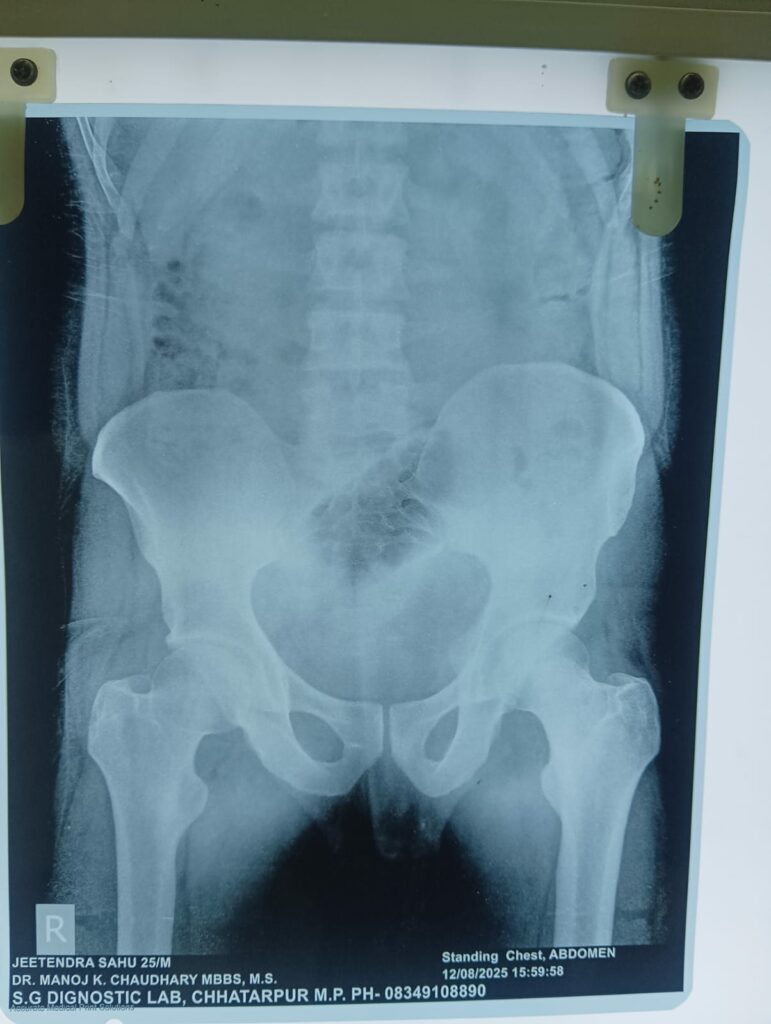

छतरपुर: Chhatarpur News: जिला अस्पताल में एक बार फिर एक अजीबोग़रीब मामला सामने आया है जिसमें नौगांव थाना क्षेत्र के रहने वाले 25 वर्षीय युवक के मलद्वार से चार दिन पहले एक प्लास्टिक की बोतल पेट में पहुंच गई।

Chhatarpur News: इसके बाद वह युवक आज छतरपुर जिला अस्पताल पहुँचा जहाँ अस्पताल के डॉक्टरों की टीम ने सूझबूझ का परिचय देते हुए सफलतापूर्वक युवक के पेट से प्लास्टिक की बोतल बाहर निकाली। डॉक्टर को युवक ने बताया कि वह मलद्वार में कीड़ों को मारने के लिए दवा लगा रहा था जो बोतल के माध्यम से दी जा रही थी। इसी दौरान वह बोतल उसके मलद्वार से अंदर जाकर पेट तक पहुँच गई।

Chhatarpur News: जिला अस्पताल के चार डॉक्टरों और नर्सिंग स्टाफ की सहायता से युवक के पेट में चीरा लगाकर बोतल को सफलतापूर्वक बाहर निकाला गया। अब तक छतरपुर जिला अस्पताल में डॉक्टरों की टीम द्वारा एक लौकी और दो प्लास्टिक की बोतलें मरीजों के पेट से निकाली जा चुकी हैं।